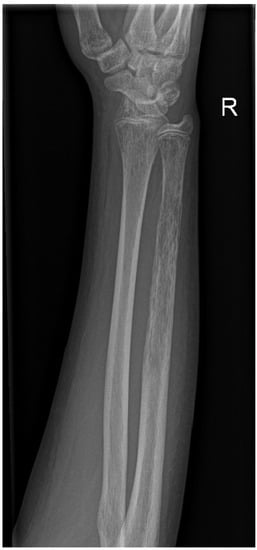

2. Case Presentation

2.2. The Course of HSCT

2.3. Early Relapse and the Final Course of the Disease